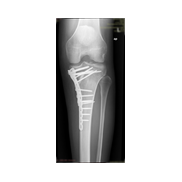

Görüntüleri büyütmek için resmin üstüne tıklayınız.